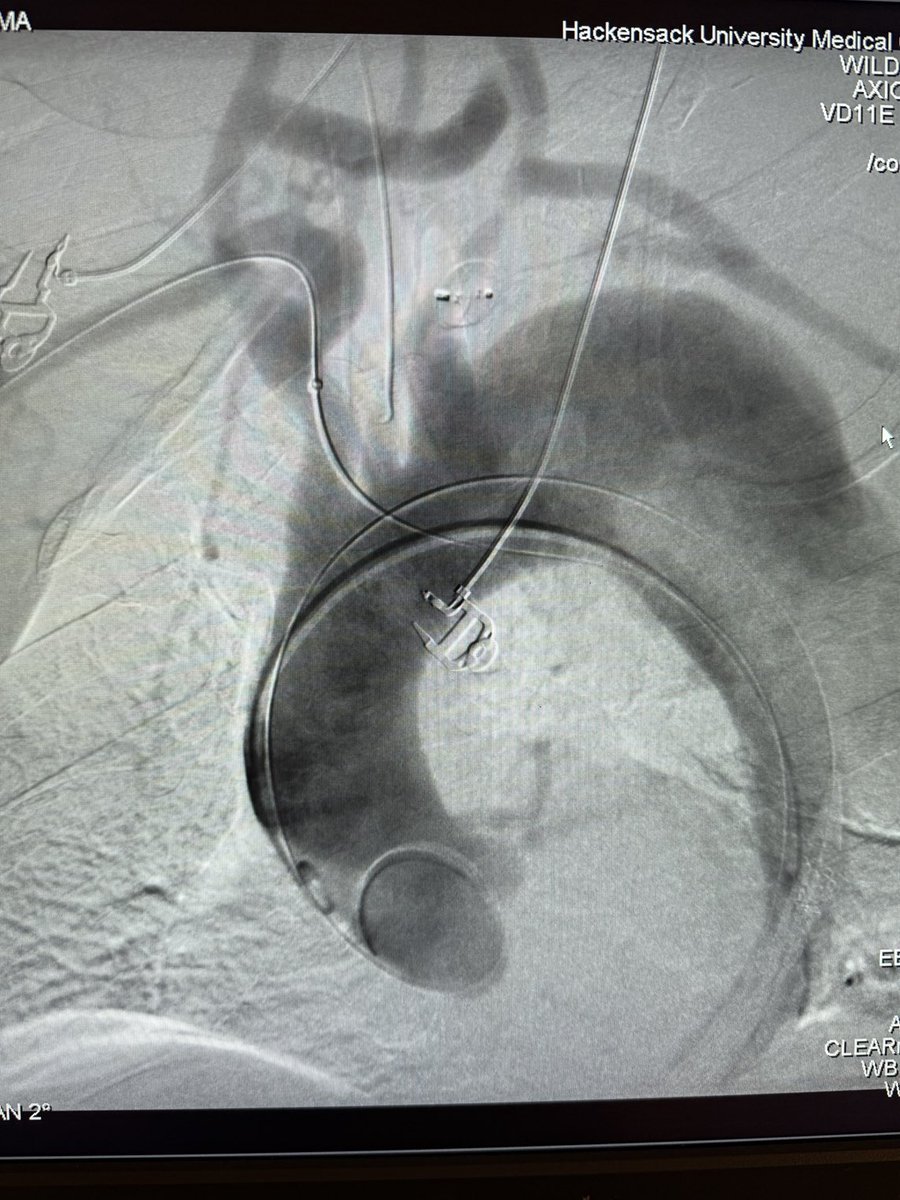

Dr Michael Wilderman

Chief of Endovascular Surgery and Co-Director of Aortic Center at Hackensack University Medical Center